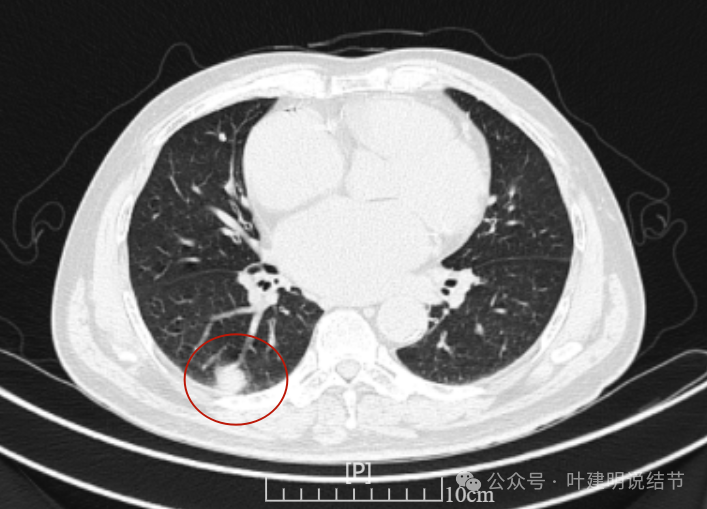

右上没有明显变化,仍考虑良性可能性大。

左下也考虑良性,与2022年无明显变化。

你的结节,对比各次的影像,原来的肺多发结节主要病灶是右上叶与左下叶这两处,其他过小。直到2022年8月,右下这处均不明显的。2023年没查,今年突然发现。首先几点:1、原有的结节没有明显进展,实性且小,考虑是良性的;2、右下结节原来没有,这次检出是新发的;3、两肺多发结节必不是右下这处新检出的病灶转移的(因为它们原来就有,右下这处是新发的)。右下这处的特点则有以下几点:1、病灶实性密度,磨玻璃成分不明显,但总体上并不是具有强收缩力或显著膨胀性的,与恶性程度很高的肺癌似乎不符合;2、表面不平毛糙,但毛刺样征并不锐利,紧邻胸膜也无明显胸膜牵拉凹陷,不是典型恶性的影像表现;3、口服消炎无好转,不像普通急性炎症;4、纵隔窗上见病灶内部密度低,周围的密度高些,中间更像坏死或液性密度。但这么小的肿瘤容易中间缺血性坏死吗?显然这与肿瘤恶性程度高而中间乏血供而坏死是不符合的。而这种表现与肉芽肿性炎伴坏死比较符合;5、病灶与胸膜紧邻,胸膜侧在纵隔窗上见基较宽并有胸膜增厚,这与炎性改变更为符合。我的感觉总体上倾向肉芽肿性炎可能性大,建议完善结核与隐球菌方面检查,并同时CT引导下穿刺活检(这个位置穿刺容易也风险小,又能取得病灶依据)。若有结核或隐球菌方面阳性结果,请内科医生按相应结果治疗;若均阴性,且穿刺也未见癌细胞,则可考虑3个月左右复查随访,当然也可直接局部胸腔镜下局部切了化验,既达诊断目的,也去除病灶。这要你自己酌情考虑选择。意见供参考!